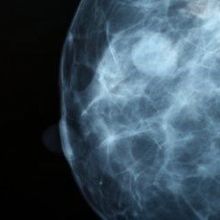

DNA Methylation Could Predict Ovarian, Breast Cancers

A pair of new studies finds that analyzing material from a Pap smear can reveal tumor risk in distant parts of the body, potentially allowing early interventions.